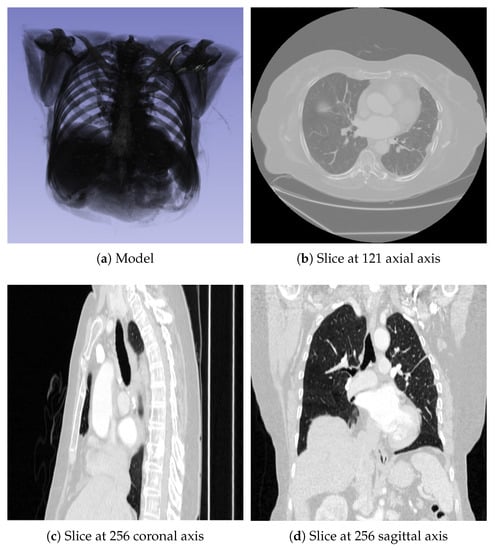

The digital CT model dataset was obtained from [27]. We extracted 45 projections from the dataset with a resolution of , as shown in Figure 5. This model serves as a benchmark for CBCT reconstruction. In addition to FDK, OS-SART, ASD-POCS, and OS-ASD-POCS, comparisons were made.

Figure 5.

CT Model: (a) Model in three-dimensional view; (b–d) Slices of the model in the axial, coronal, and sagittal planes, respectively.

Reconstruction results are presented in Figure 6, with the 121st slice in the axial direction chosen for comparison due to its information richness. The CT model slice is shown in Figure 6a. Similarly to Experiment 1, Figure 6b reveals that FDK and OS-SART algorithms exhibit relatively severe streak artifacts, while ASD-POCS and OS-ASD-POCS suppress artifacts but blur the edges. From the reconstruction results, it is evident that the proposed method outperforms the other algorithms in Table 2.

Figure 6.

The CT reconstruction (slice 121): (a) CT model, (b) FDK, (c) OS-SART, (d) ASD-POCS, (e) OS-ASD-POCS, (f) proposed method.